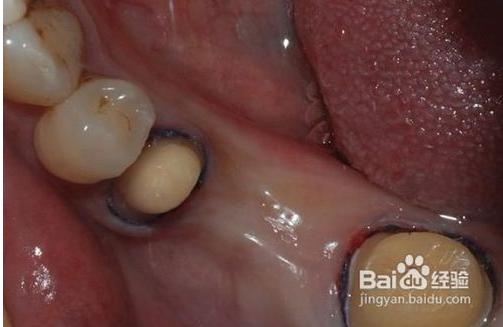

1、磨牙

為了使完成后的烤瓷牙冠戴入后不超過原始狀態(tài)的外牙厚度,一般做烤瓷牙要磨除部分自然牙。另外為了使假牙順利就位并獲得良好的固位,要將基牙制備成一定的形狀?;乐苽涞暮脡?,關系到假牙是否容易戴入以及牢固性。

QQ圖片20150818101746.png